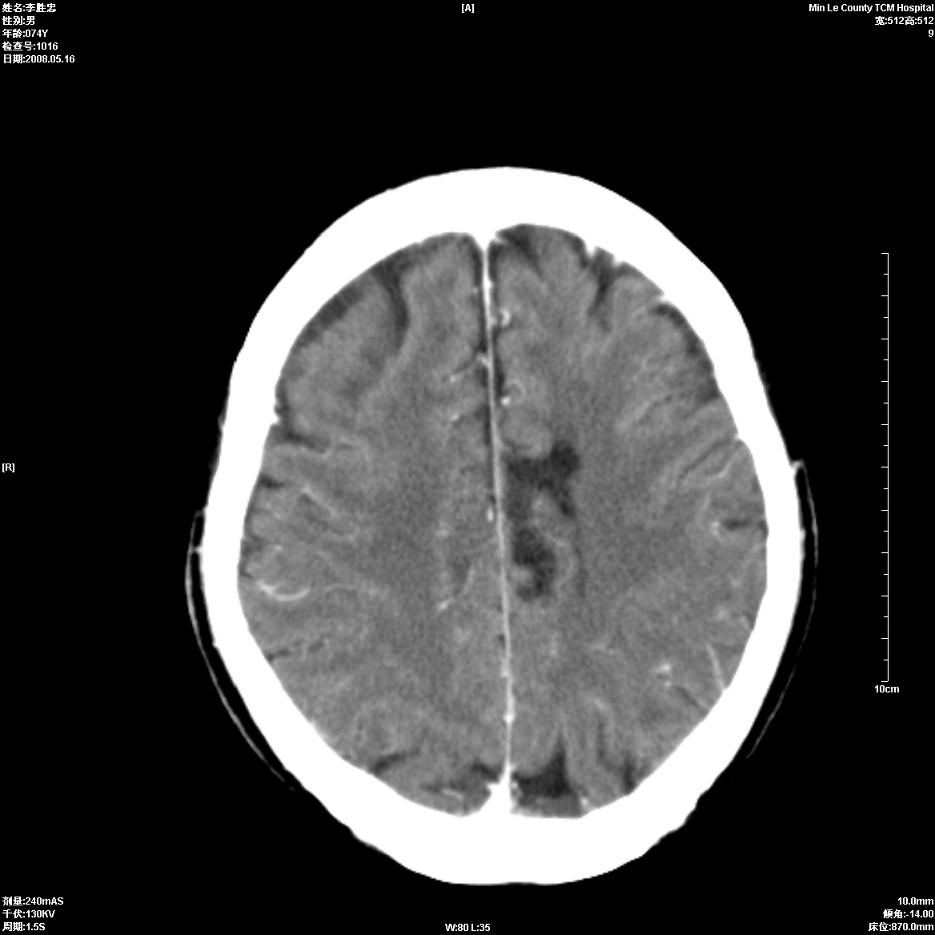

以下是引用hhcckk在2008-5-30 14:26:00的发言:[br]病灶跨中线,有占位效应,强化不明显,考虑胼胝体区低级别的星形细胞瘤可能性大,建议mr检查